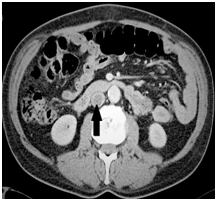

With an iron deficiency anaemia and a concern for an occult GI bleed, endoscopy was performed that showed grossly abnormal, thickened gastric folds in the body and multiple polypoid lesions in the antrum with scattered blood throughout (Figures 3) (Figure 4).

Figure 4Polypoid lesions in fundus.